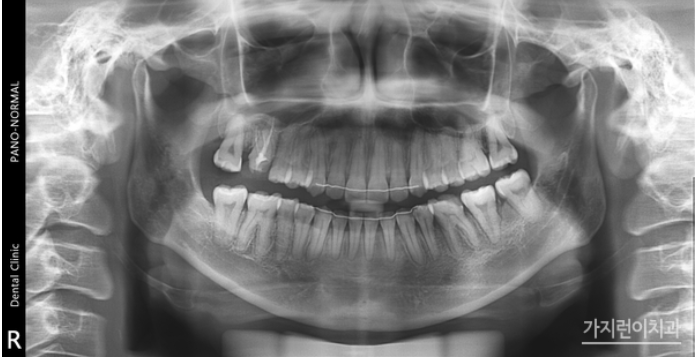

해당 환자분의 경우는 사랑니를 어금니로 대체하는 교정을 계획했었는데요. 위 사진을 보면 사랑니를 세우면서 임플란트를 식립하지 않고 발치 공간을 닫았습니다. 하악 좌측의 사랑니를 효과적으로 세우기 위해 modified bonded cantilever (MBC) spring을 사용했는데요.

상하악 중심선도 잘 맞추었고 교합도 정상교합으로 맞춘 것을 볼 수 있습니다. 하악 사랑니도 잘 세워진 것을 눈으로 확인할 수 있을 정도가 되었는데요. 더 쉽게 보기 위해 교정 전후의 엑스레이 사진도 확인해보겠습니다.